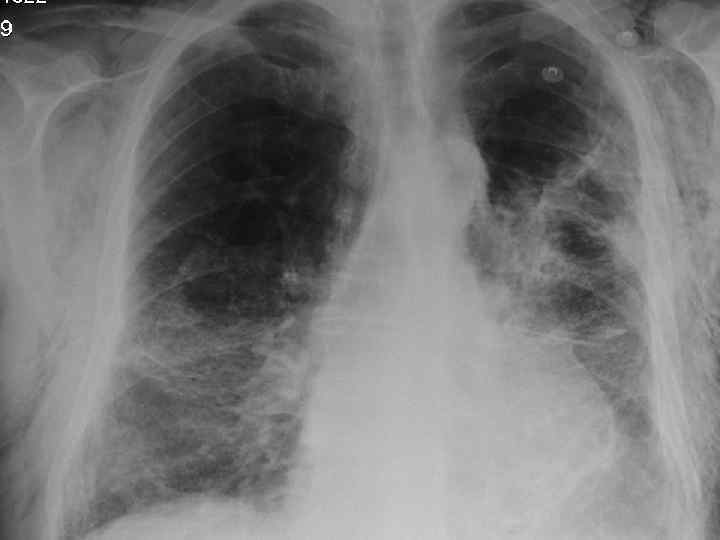

Clinical features n Progressive breathlessness n Cyanosis n Pulmonary hypertension/cor pulmonale n Clubbing n Bilateral fine end insp. Crackles n X-ray shows ground glass appearance

Investigations n Chest X-ray n High res. CT scan n Respiratory function tests n Blood gasses n ANF, RF, ESR n Bronchoalveolar lavage n Biopsy

Differential diagnosis n Extrinsic allergic alveolitis n Bronchiectasis n Chronic LHF n Sarcoidosis n Industrial lung disease n Lymphangitis carcinomatosa